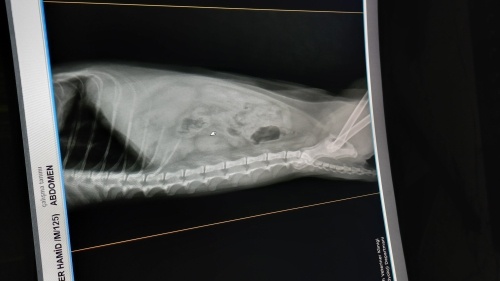

Zoro isimli 2.5 yaşında bir kedim var. Yaklaşık 10 gün önce dışkı yapamama sorunu yaşadığı için veterinere götürdüm. Röntgen ve takip istendi ama son iki gündür durumu daha da kötüleşti, hiç sakinleşmiyor.

Rontgene göre kolon ve rektum tamamen dolu ve megakolona doğru giden bir tablo var. Bir süredir dışkının bağırsaklarda biriktiği açık. Lavman veya rektal boşaltma yapılmadı ise acil yapılmalı.

Serum+evde devam tedavisi olarak laktuloz. Mama değişecek sorun düzelene kadar mümkünse gastro yaş mama, yaş mama sevmiyorsa Royal Canin fibre response veya Virbac gastro kullanılacak.

Başa dönüyorum, lavman yapılmadı ise hekiminizi değiştirin. Yazdığım her şey yapıldı ise bu halde ameliyat şart olur.